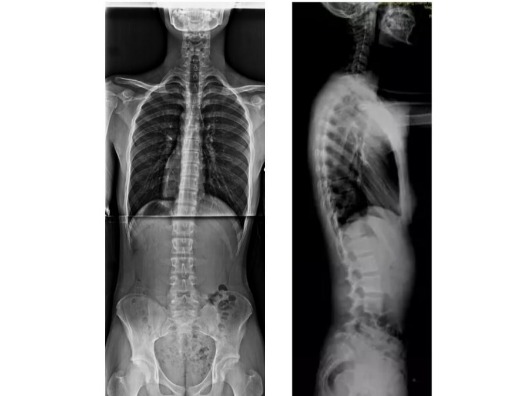

3. 全脊椎 X 光片(確診與分析的關鍵)

X 光才能真正看到脊椎骨頭的角度與排列,並做出完整診斷。

2. 正面與側面都要拍

-

正面 X 光片:用來測量側彎角度(如柯布角)、是否有肋骨變形、側彎類型等。

側面 X 光片:能看出脊椎正常的前後弧度是否存在(如胸椎和腰椎的生理曲線),對治療策略非常重要。